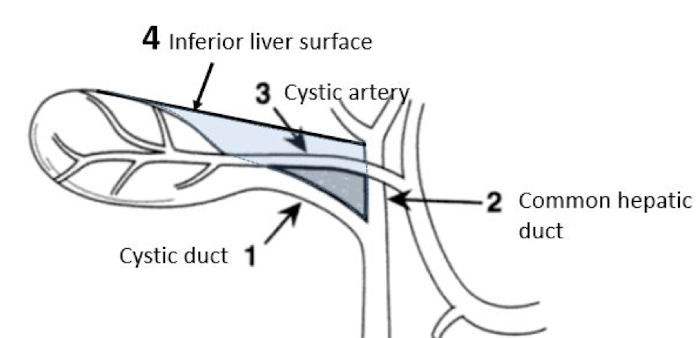

Calot’s triangle

Vessels and nerves at risk for injury in anterior abdominal wall